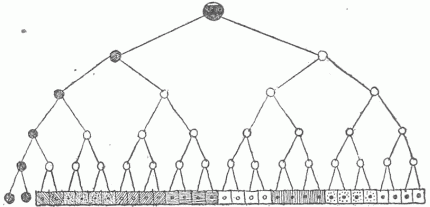

- Inheritance As A Factor In Disease.—The Process Of Cell Multiplication.—The Sexual Cells Differ From The Other Cells Of The Body.—Infection Of The Ovum.—Intra-Uterine Infection.—The Placenta As A Barrier To Infection.—Variations And Mutations.—The Inheritance Of Susceptibility To Disease.—The Influence Of Alcoholism In The Parents On The Descendants.—The Heredity Of Nervous Diseases.—Transmission Of Disease By The Female Only.—Hemophilia.— The Inheritance Of Malformations.—The Causes Of Malformations.—Maternal Impressions Have No Influence.—Eugenics.